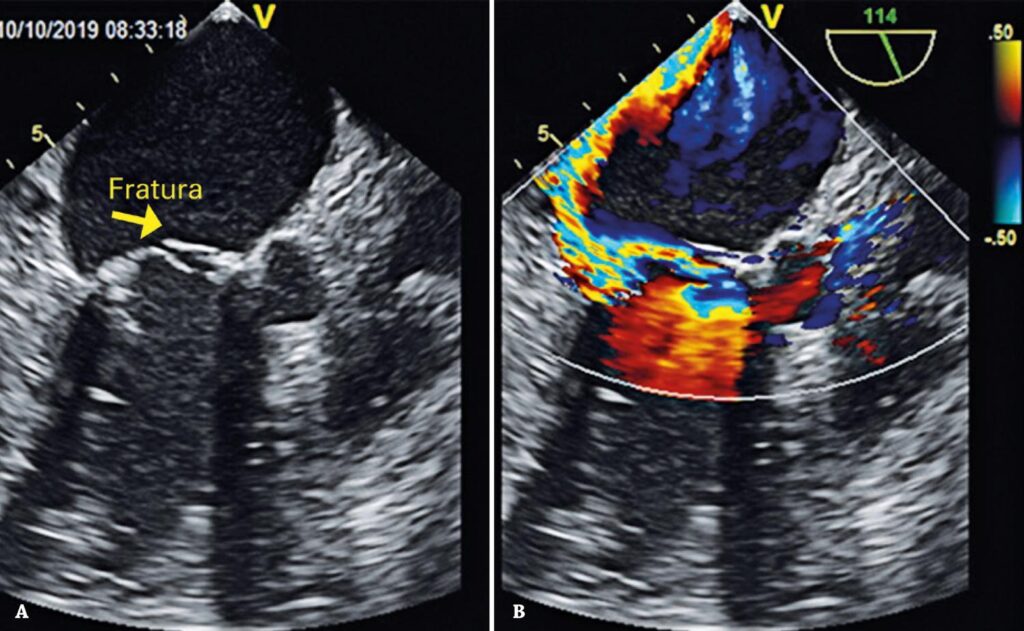

Figura 1

Ecocardiograma transesofágico pré-procedimento. (A) Evidência de fratura de prótese valvar mitral biológica prévia. (B) Doppler colorido evidenciando refluxo mitral importante.